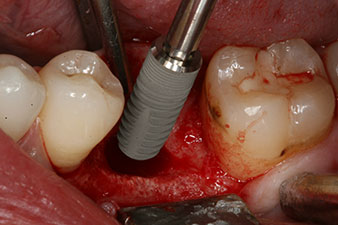

Implantat

Figura 3: Después de realizar la preparación con el motor de implantes Implantmed, se enroscó mecánicamente un implante (diámetro 4 mm, longitud 12 mm) con un torque de 43 Ncm.

Tras la extirpación minuciosa del tejido de granulación, se incorporó el implante tal como se había planificado (blueSky, bredent).